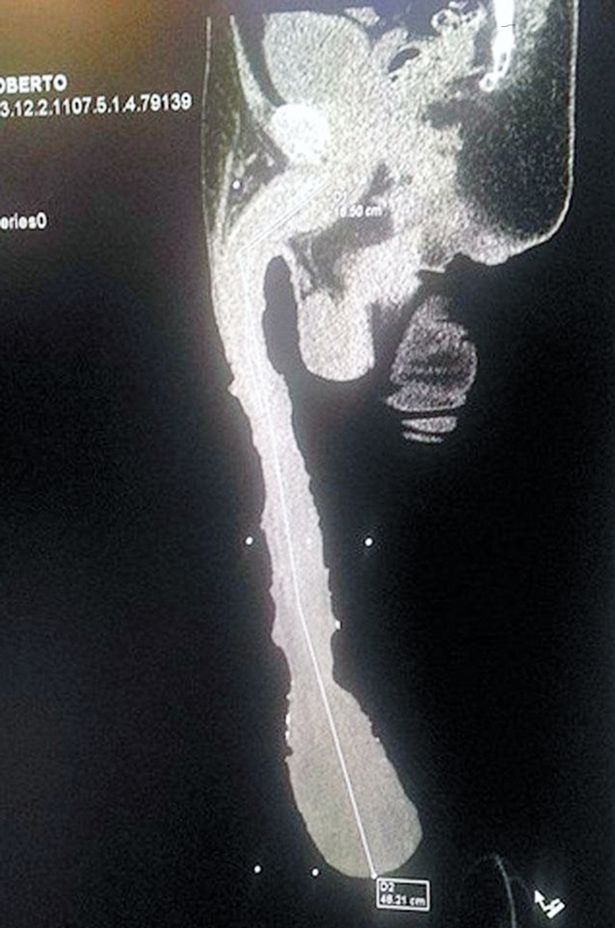

Ο Ρομπέρτο Καμπρέρα υποστηρίζει πως είναι ο πιο προικισμένος άνδρας στον κόσμο. Με 48 εκατοστά μήκος μάλλον έχει δίκιο. Όμως καμία γυναίκα, όπως λέει ο ίδιος δε δέχεται να κάνει σεξ μαζί του γιατί τρομάζουν από το μέγεθος του ανδρισμού του.

Ο 52χρονος κάνει επίσης και τα παράπονά του γιατί δεν έχει αναγνωριστεί επισήμως από το βιβλίο Γκίνες. Βέβαια οι γιατροί έχουν προσφερθεί να τον βοηθήσουν να αποκτήσει ένα φυσιολογικό μέγεθος έτσι ώστε να μην έχει όλα αυτά τα προβλήματα. Οι ίδιοι μάλιστα επιβεβαιώνουν ότι η ακτινογραφία που περιφέρει ο Καμπρέρα είναι αληθινή σημειώνοντας όμως ότι μόνο τα 15 εκατοστά είναι ανδρικό μόριο και όλο το υπόλοιπο είναι απλώς δέρμα.